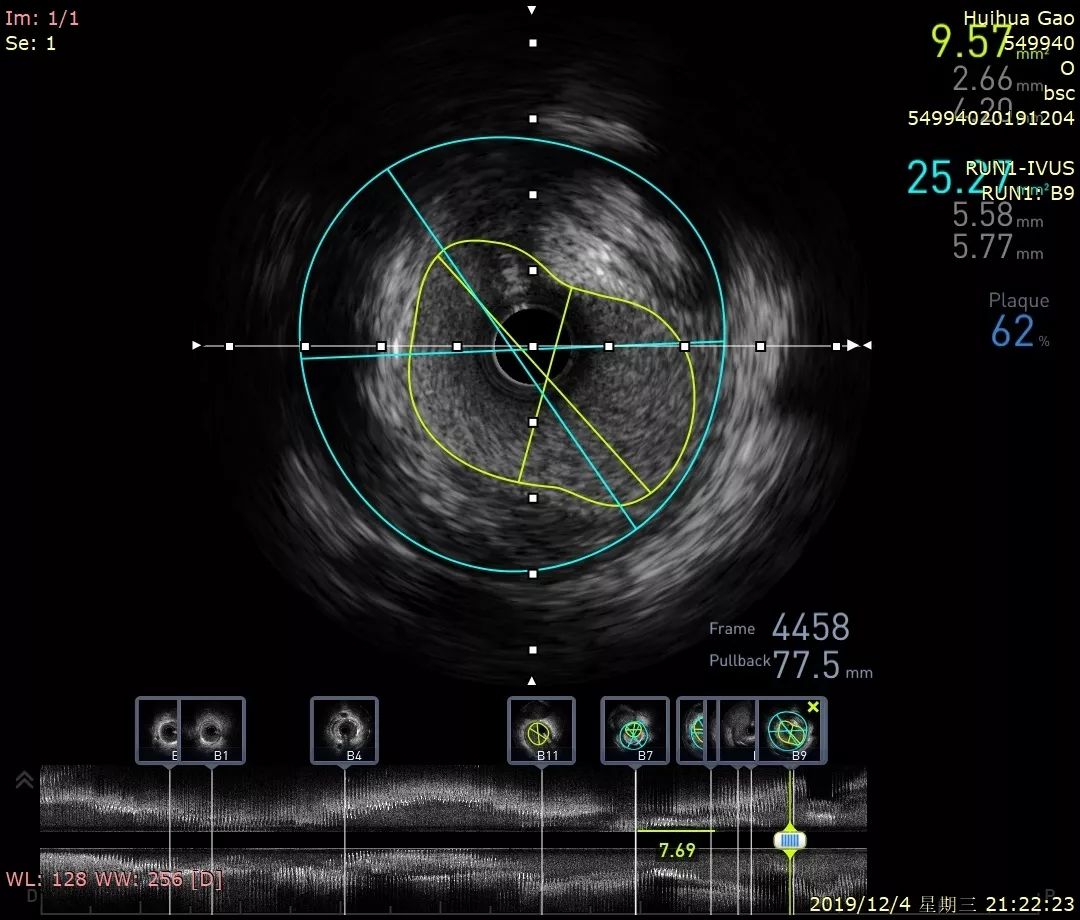

祝贺血管内超声(ivus)落户吉林市人民医院

图片尺寸1686x846